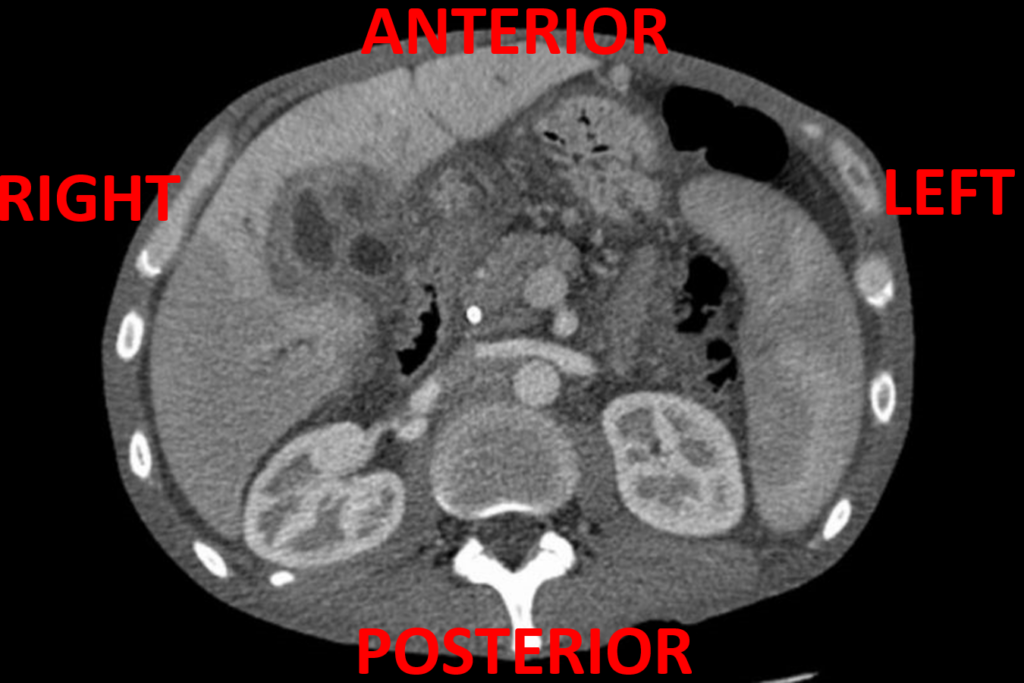

Abdominal CT Basics • LITFL • Radiology library When To Use Contrast Vs Non Contrast Ct 3 it is useful in the. If you have questions about ordering your patient’s ct, we. When is iv contrast used? Ct of the abdomen and pelvis (with the exception of a ct stone study and ct angiography) will receive an oral contrast prep. These suggestions are general guidelines that apply to the use of contrast for ct exams provided. When To Use Contrast Vs Non Contrast Ct.